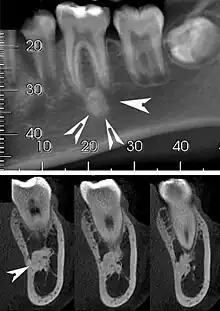

| Top: A hyperdense round lesion located under the apex of a non-infected tooth. Bottom: The lesion is separated from the root of the adjacent tooth by a visible periodontal membrane.[1] | |

Idiopathic osteosclerosis, also known as enostosis or dense bone island, is a condition which may be found around the roots of a tooth, usually a premolar or molar.[2] It is usually painless and found during routine radiographs as an amorphous radiopaque (light) area around a tooth. There is no sign of inflammation of the tooth, and if the island is associated with the root the periodontal ligament space is preserved.[2]

Well defined, rounded or triangular radiodensity, that is uniformly opaque. There is no lucent component. Found near the root apex or in the inter-radicular area. Root resorption and tooth movement are rare. If it blends into bone cortices, it does so with no expansion or thinning.[2]